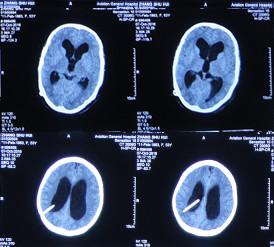

患者2014年6月20日出现持续头晕的症状,不能自行缓解,于2014年6月24日和6月26日分别就诊于甘肃省平凉县某医院和陕西省西安某医院,进行了头颅MRI和头颅CT示脑室扩张,脑积水(图-1、图-2)。

图-1:2014年6月24日头颅MRI

图-2:2014年6月26日头颅CT